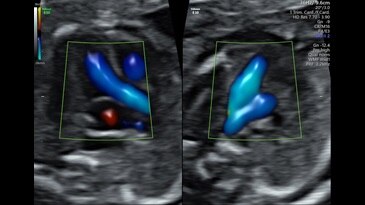

Radiantflow

Новое поколение цветового допплера Radiantflow упрощает и ускоряет исследование, улучшает визуализацию мельчайших сосудов. Алгоритм построения изображения учитывает амплитуду допплеровского сигнала, что позволяет получить изображение схожее с 3D.

SlowFlowHD

Расширьте свои представления о возможностях допплеровского картирования с помощью технологии SlowflowHD, созданной для визуализации перфузии в сосудах самого малого размера.